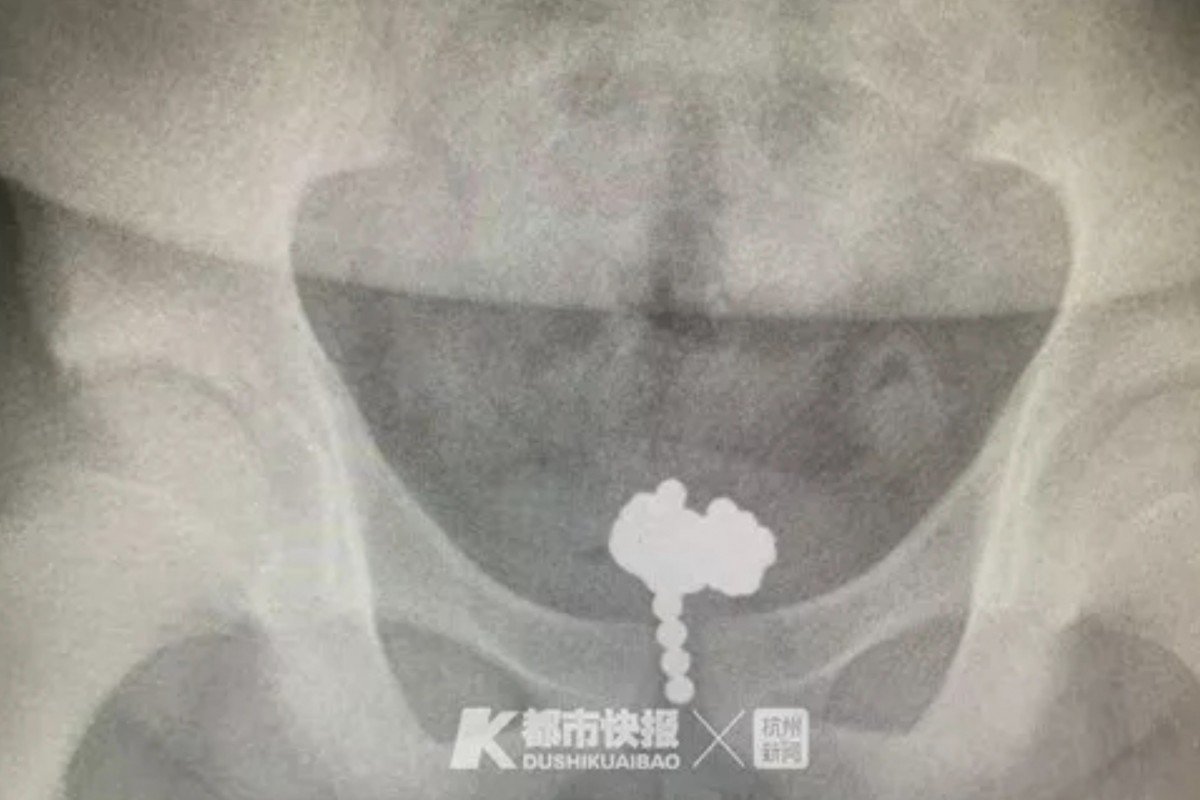

Phim X-quang chụp ổ bụng khiến các bác sĩ ngạc nhiên vì phát hiện một chuỗi những viên hình tròn trong bàng quang của bệnh nhân. Cậu bé thừa nhận đã nhét những viên bi từ trường vào dương vật vì tò mò.

Phim X-quang cho thấy vị trí của những viên bi trong bàng quang - Ảnh: Guancha. |

Sau 2 giờ làm phẫu thuật nội soi, các bác sĩ đã lấy ra 70 viên bi, mỗi viên có đường kính 5 mm, từ bàng quang của bệnh nhân.